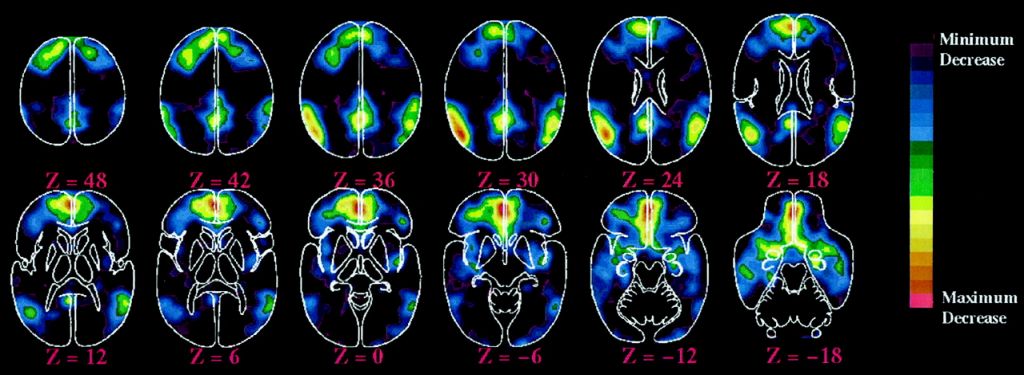

Pentru a vedea ce se întâmplă, activitatea creierului unui număr de 27 de copii în jurul vârstei de 4 ani a fost examinată pe parcursul celor trei tipuri de ”lectură” a unei povești cu ajutorul unui MRI** (aparat de rezonanță magnetică).

În timp ce copiii erau atenți la povești, aparatul MRI le scana creierul pentru a vedea activitatea în anumite zone, activitatea rețelelor neuronale și conexiunile dintre rețele.

“Am intrat în acest studiu având în minte ideea de a vedea modul în care rețelele creierului sunt influențate de poveste”, explică Hutton. Una din zonele observate a fost cea a limbajului. O alta a fost cea a percepției vizuale. Cea de a treia este numită zona imaginației vizuale. Iar cea de a patra este rețeaua default mode (funcționare implicită), pe care Hutton o denumește “sediul sufletului și al reflecției interne – care arată în ce măsură ceva contează pentru tine.”

În condițiile audiției audio simple (care este ”prea rece”) au fost activate rețelele limbajului, dar conectivitatea generală cu celelalte zone a fost mai slabă. “Existau mai multe dovezi că copilul se forța să înțeleagă.”

În condițiile urmăririi desenului animat (care este ”prea fierbinte”) s-a observat multă activitate în zonele și rețelele percepției audio și vizuale, dar nu foarte multe conexiuni cu variatele rețele ale creierului. ”Rețeaua limbajului lucra intens pentru a ține pasul cu povestea,” spune Hutton. “Interpretarea noastră a fost că filmul animat face munca în locul copilului. Copiii cheltuiau majoritatea energiei doar pentru a-și da seama ce înseamnă ceea ce văd/aud.” În această situație, înțelegerea poveștii a fost cea mai slabă.

În condițiile vizualizării ilustrațiilor dintr-o carte în timp ce urmăresc audio povestea, s-a dovedit că această combinație este cea potrivită.

Atunci când copiii au putut vedea ilustrațiile, intensitatea activității rețelei neuronale a limbajului a scăzut puțin în comparație cu activitatea din zona percepției audio. În loc să acorde atenție doar cuvintelor, spune Hutton, înțelegerea de către copii a poveștii a fost structurată de indiciile oferite de imagini.

Cel mai important, în situația unei cărți ilustrate, cercetătorii au văzut o conectivitate crescută între și în interiorul tuturor rețelelor neuronale la care s-au uitat: percepția vizuală, imaginația vizuală, limbajul și acea default mode (reflecția internă).